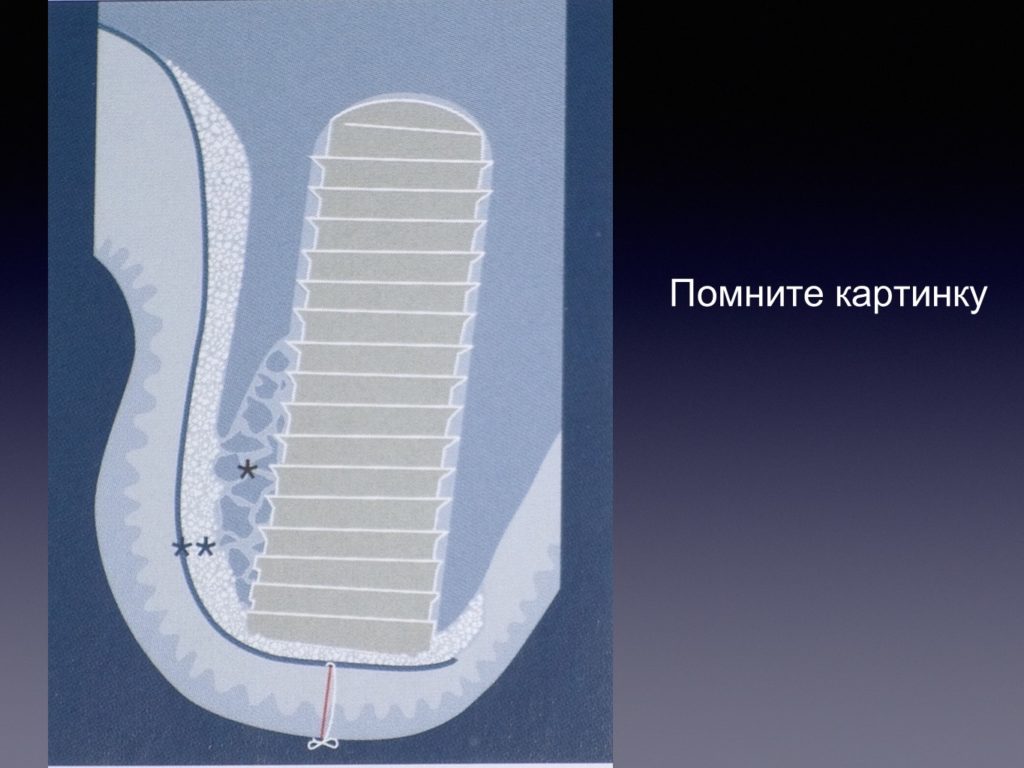

Принцип направленной костной регенерации. Костная регенерация под защитой мембраны Биоматрикс

Принцип направленной костной регенерации. Костная регенерация под защитой мембраны Биоматрикс

Принцип направленной костной регенерации. Костная регенерация под защитой мембраны Биоматрикс